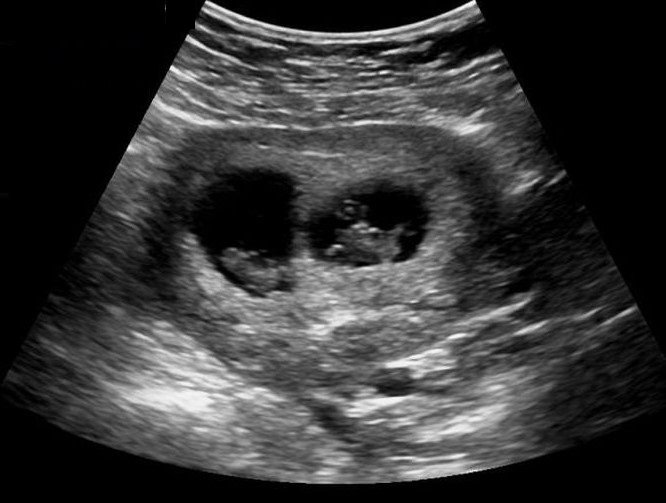

These are usually the 2D black and white scan images you are probably used to seeing in the hospital. This is because at this early stage baby isn’t yet developed enough to see in more detail. The same technology (ultrasound machine and probe) is used later in your pregnancy but is capable of showing you much more detail once your baby is sufficiently developed, usually this is possible from around 16 weeks but best images are taken around 27 weeks. These are the high detail 3D pictures that have a golden look and feel to them.

We will provide you with a 2D ultrasound scan using the most modern technology. To help you begin your journey, keepsake images of your scan are available to purchase as either printed pictures or digitally on a USB, as are heartbeat teddy bears and we provide an approximate gestation and delivery date.